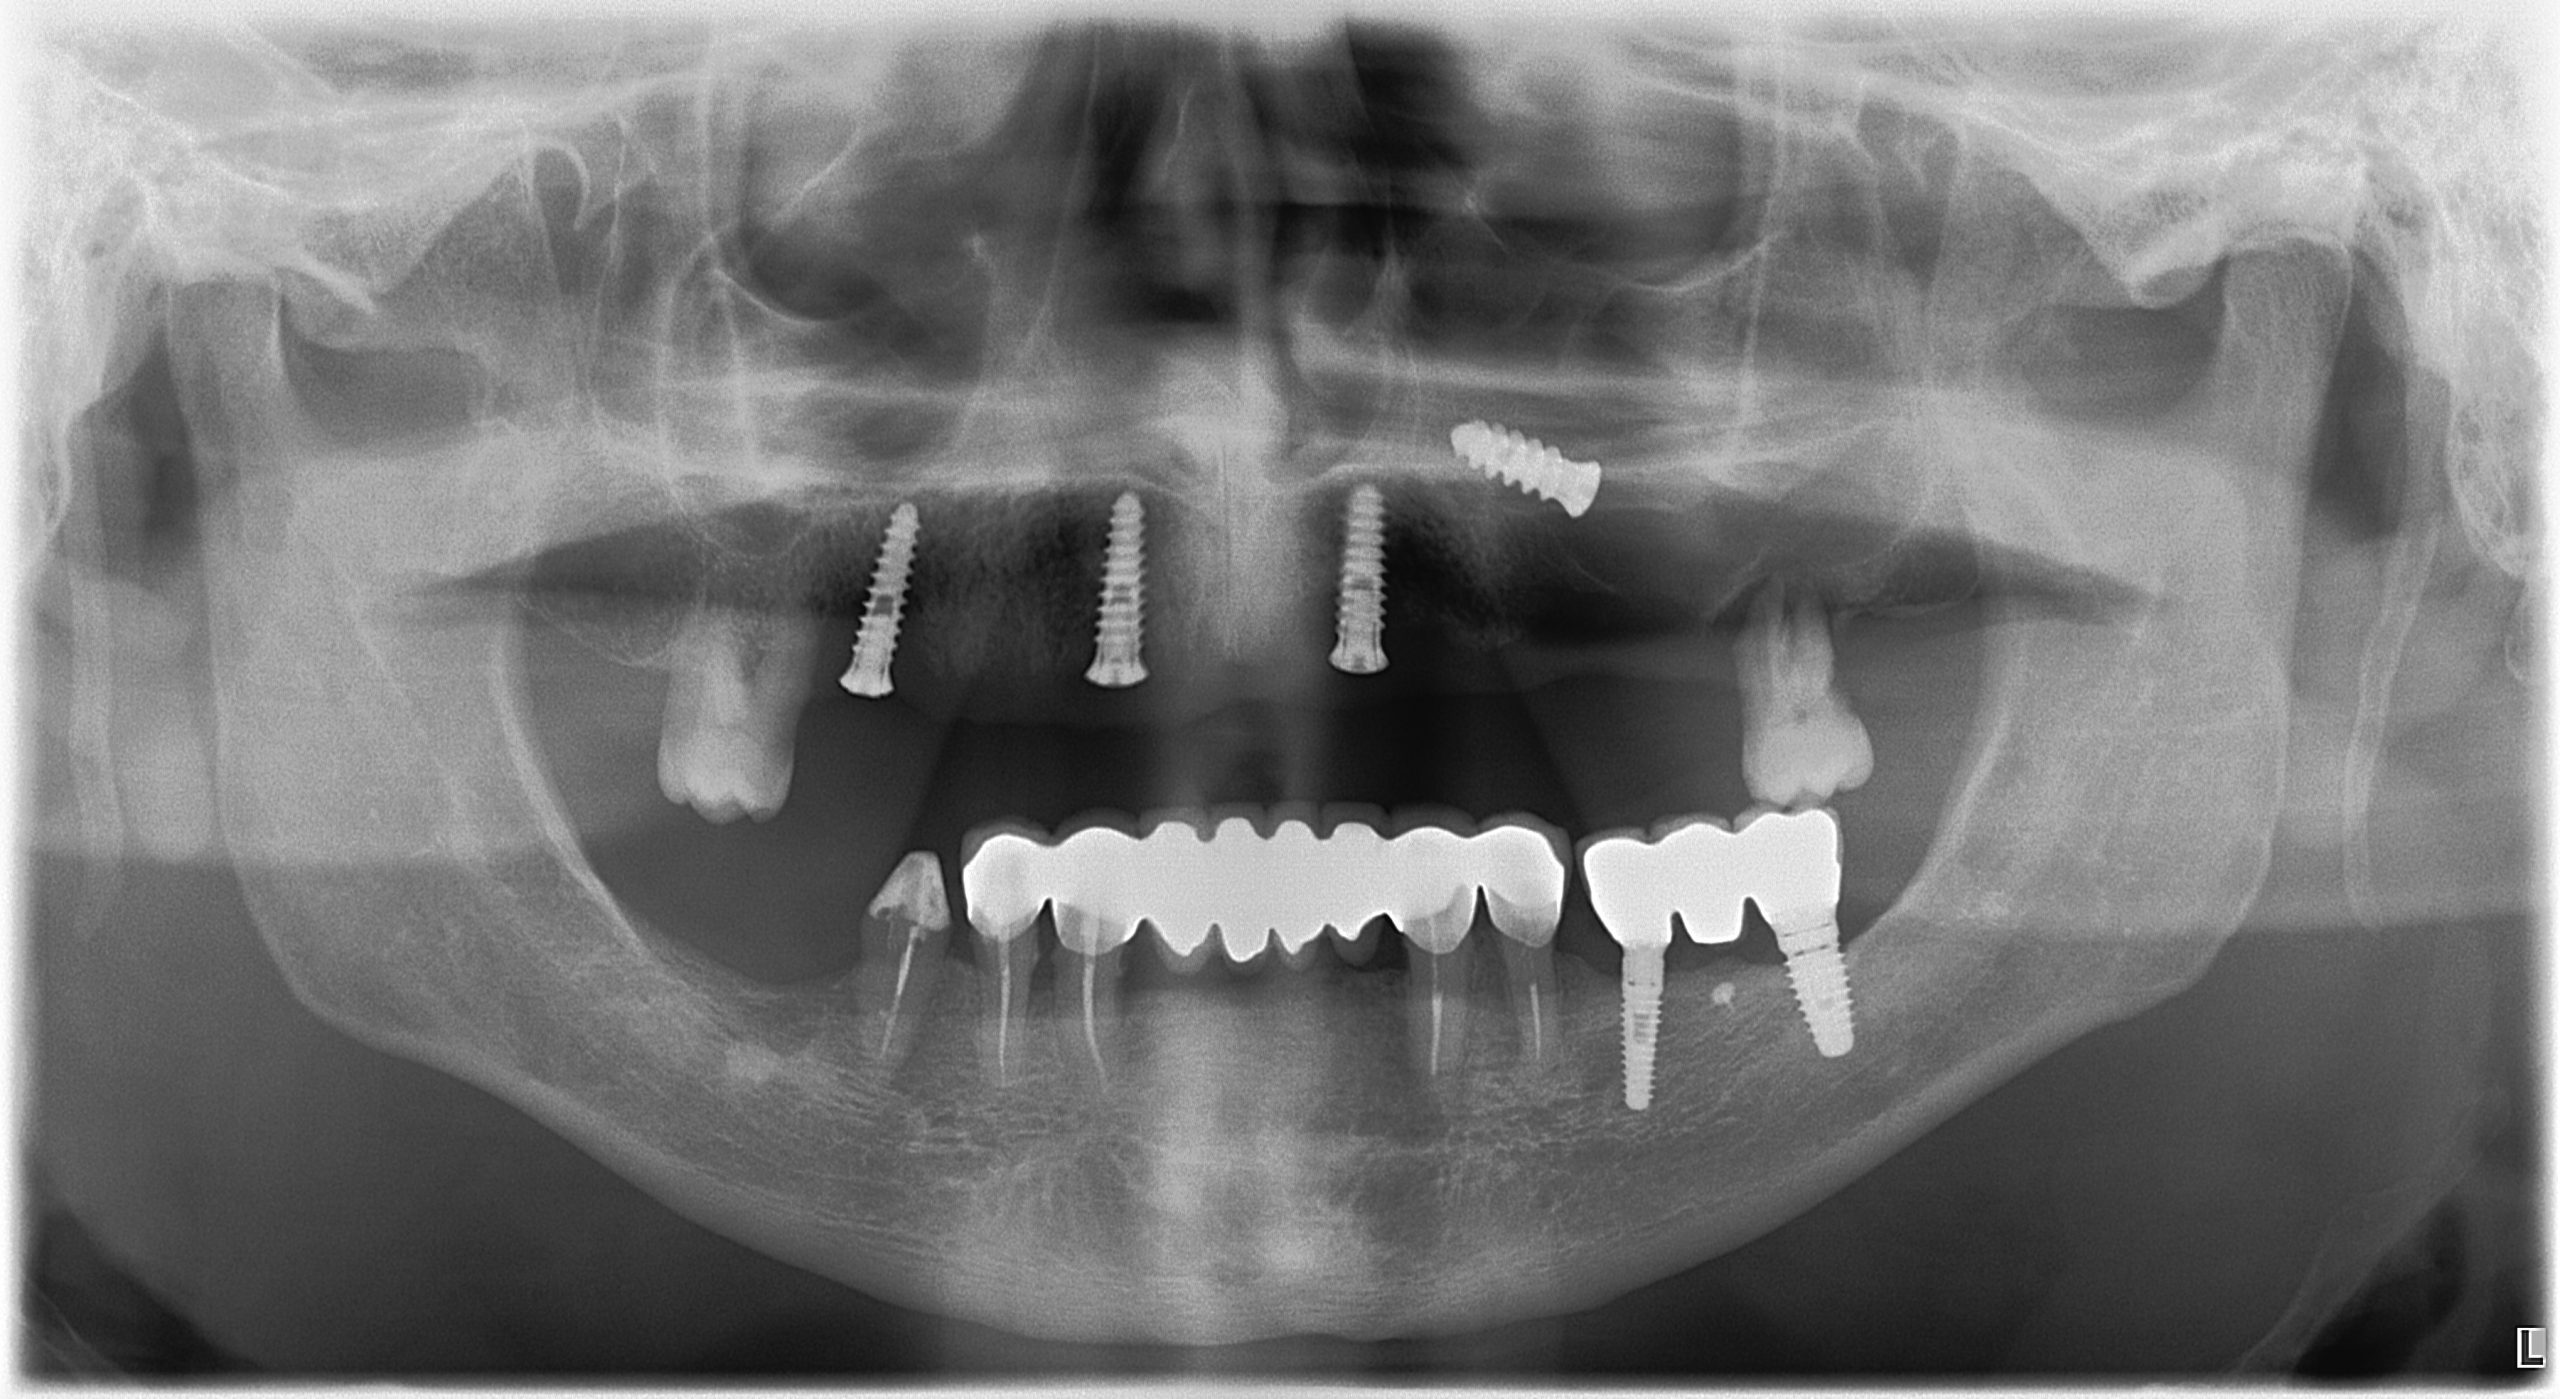

Nuovo software certificato come previsto dalla direttiva MDR 75

I software cefalometrici (software medicali) sono considerati dispositivi medici quindi soggetti al nuovo regolamento europeo MDR 75 che ne prevede la certificazione. Sirio si è prontamente adeguata alla direttiva installando il nuovo software Deltadent in possesso della certificazione come dispositivo medico di classe I m, garantendo così la reciproca sicurezza.Per informazioni: segreteria@sirioradiologiadentale.it